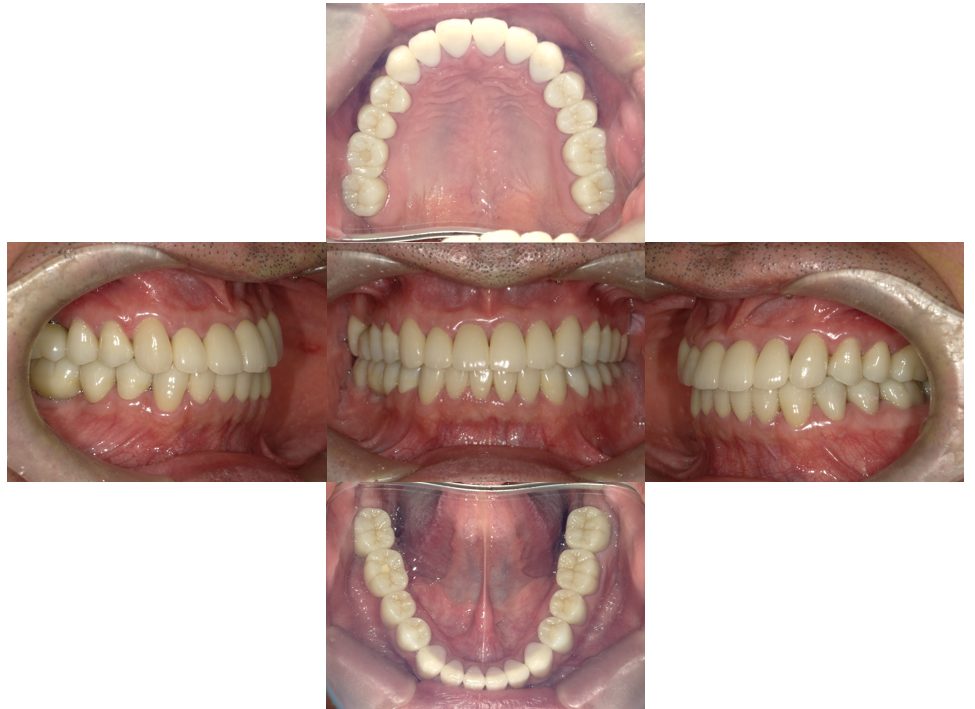

矯正治療・インプラント治療・セラミック治療の症例紹介(三隅歯科クリニック)

三隅 賢祐(三隅歯科クリニック)

症例詳細

| 主訴 | 30代女性 顎関節が痛い。見た目も気になる |

| 治療内容 | 矯正治療を行いました。 |

| 治療費 | 1,700,000円(税込み) |

| 治療期間 | 3年(矯正治療期間 2年半) |

| 治療回数 | 40回 |

| 想定されたリスク | 術前に精密な診査診断とシミュレーションを行い、インプラントを適正なポジションに埋入しておかないと、インプラント自体が矯正治療の邪魔になるリスクがあった。 |